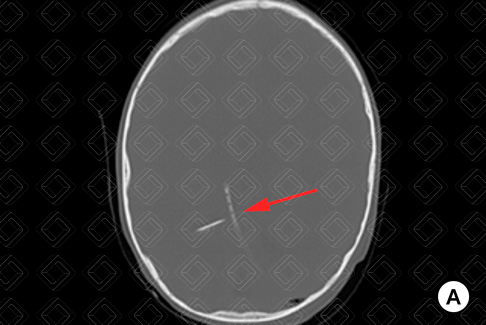

Descrição das imagens: Tomografia computadorizada do crânio: reconstruções na janela óssea (A e B) e parênquima encefálico (C). Exame realizado no paciente após troca do cateter de derivação ventricular, mostrando pequeno pneumoencéfalo (setas amarelas) adjacente à inserção do cateter. Observa-se a presença dos cateteres de derivação ventriculares (seta vermelha).